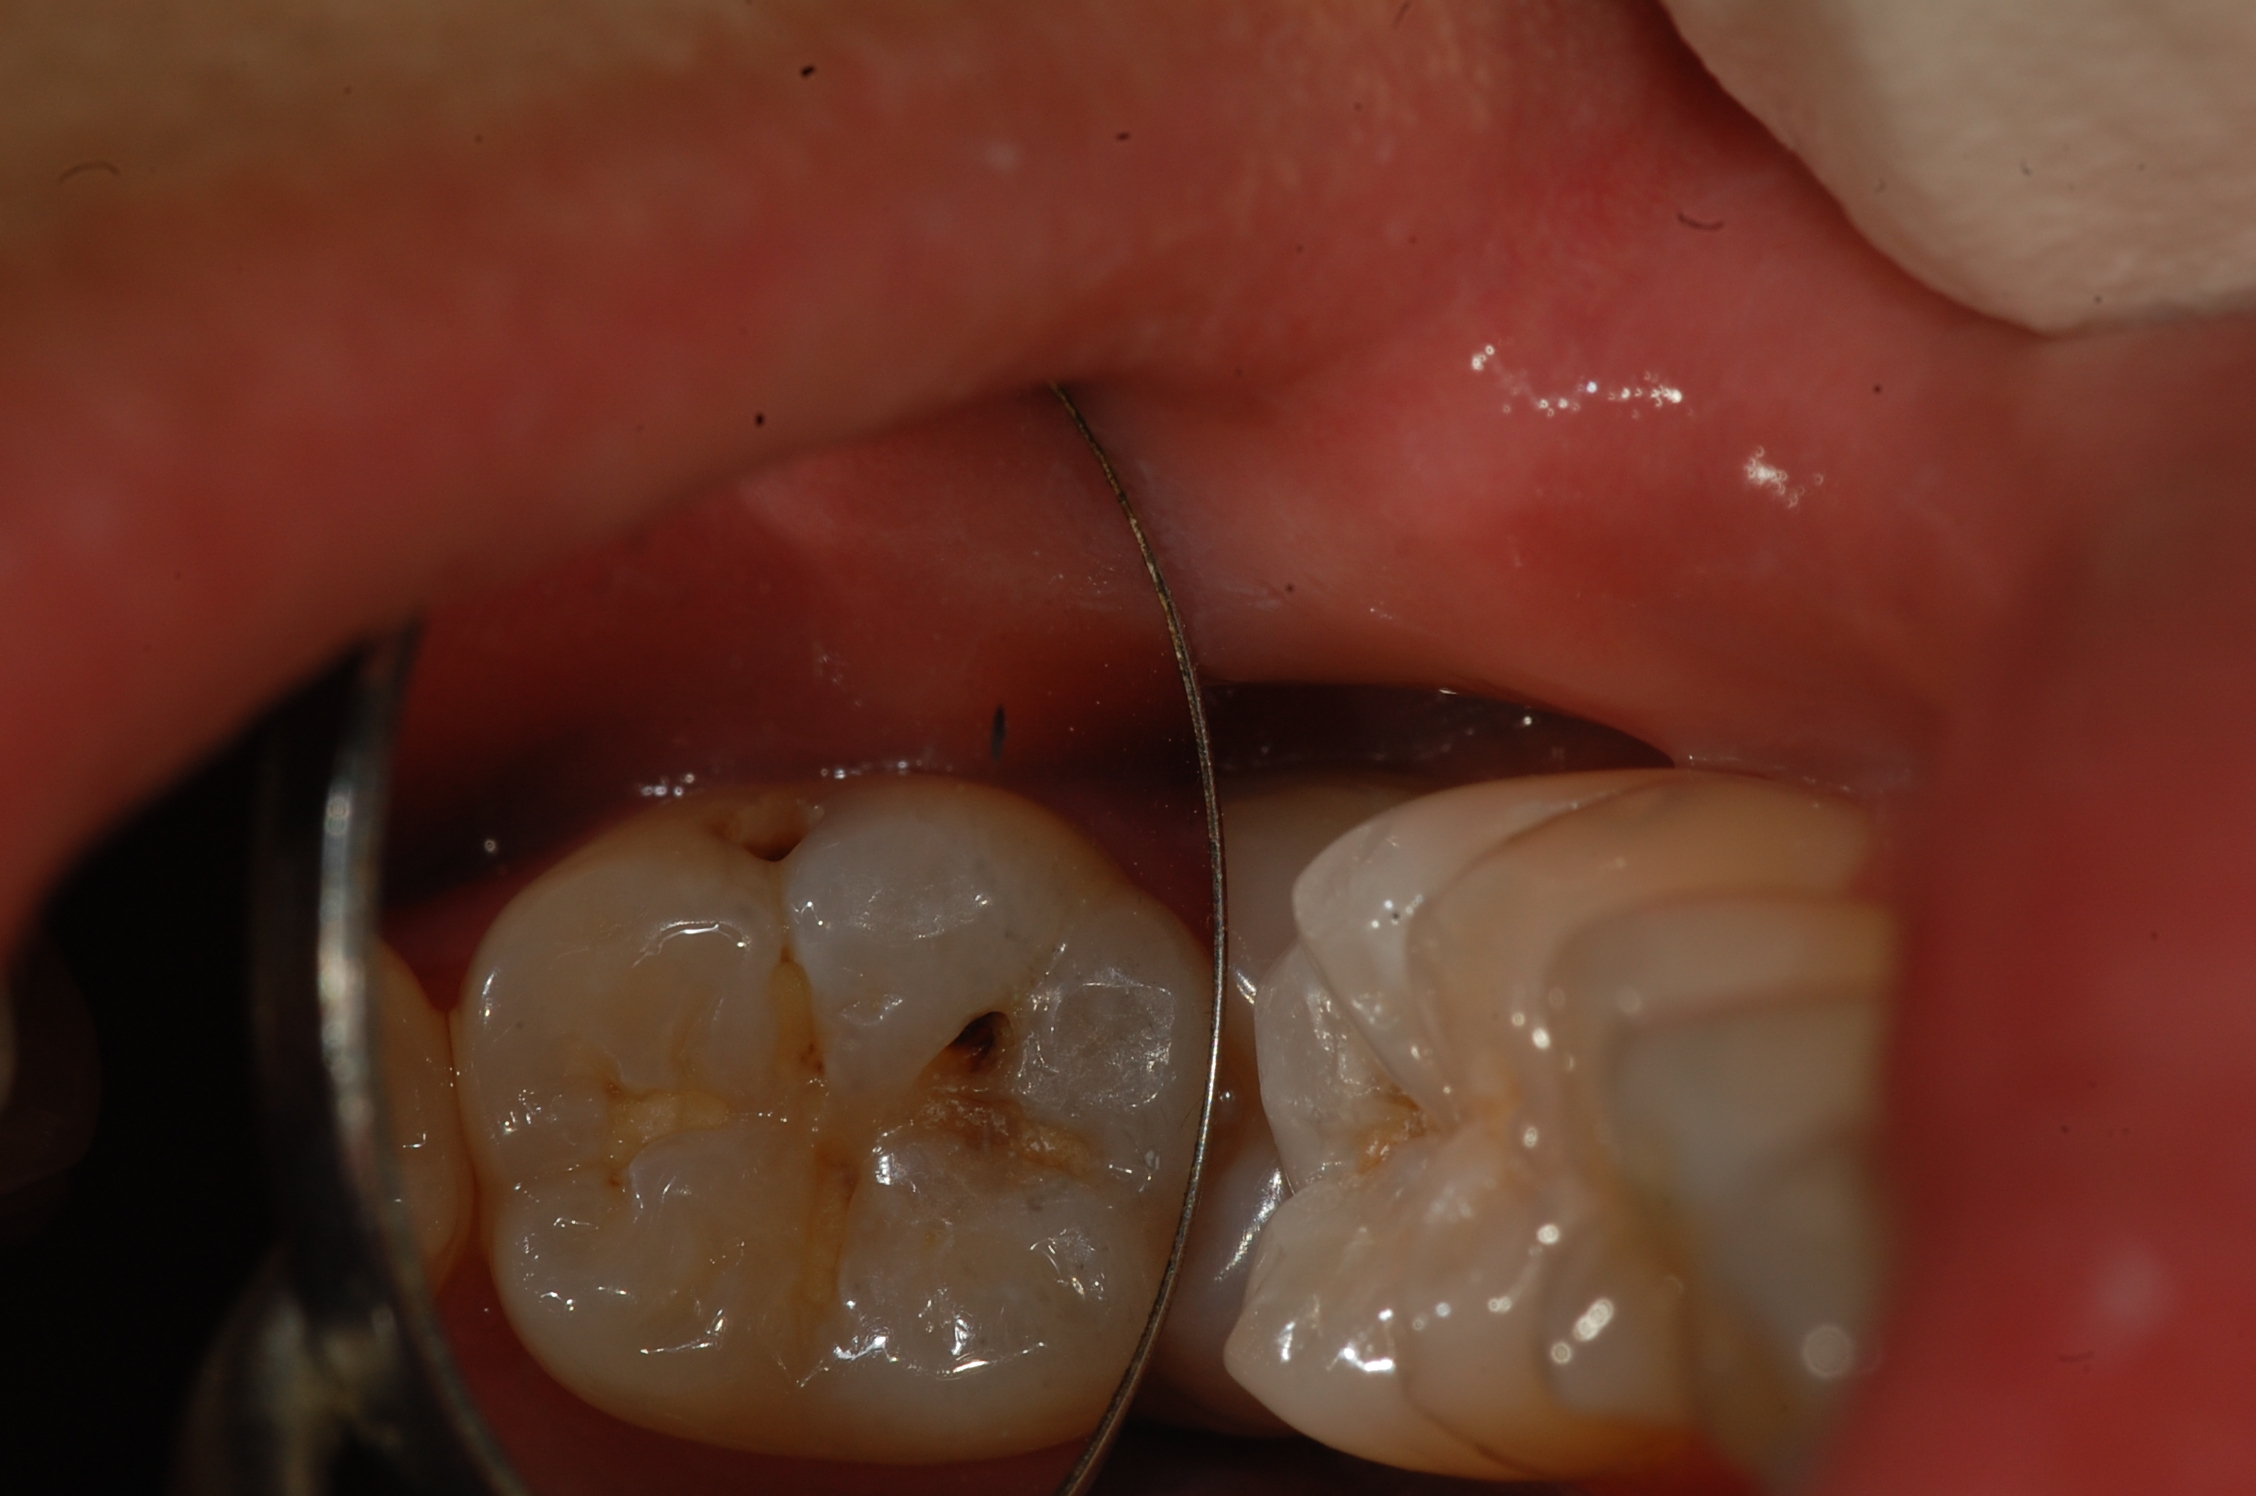

[보철,충치치료] 제목 : 하악구치

레진인레이